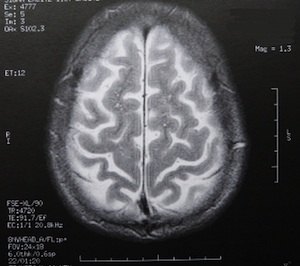

Sie sind hier: Startseite Nachrichten Wissenschaft Universität Magdeburg an einem der größten Forschungsprojekte Europas beteiligt Bild: pixelio.de/Dieter Schütz